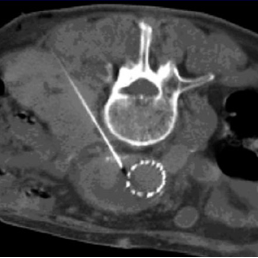

Trans-vessel Approach

Transcaval

Transarterial perigraft

Transarterial transgraft

Direct Sac Puncture Approaches

Percutaneous translumbar

Percutaneous transcaval

Percutaneous transabdominal